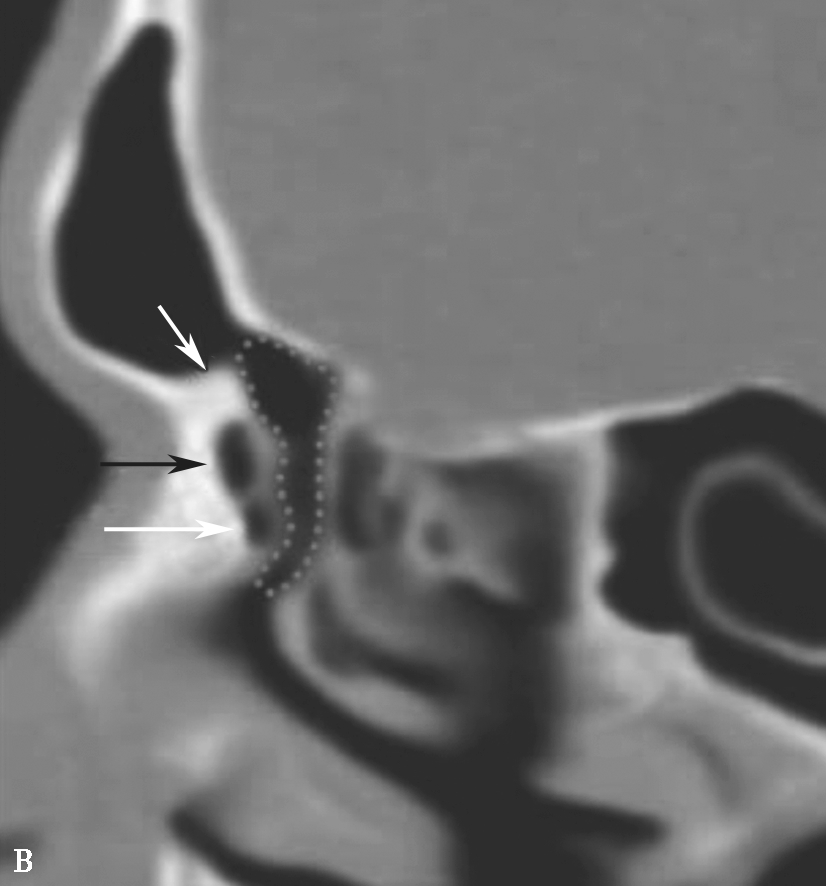

图1-3-5 筛漏斗解剖

A、B.额隐窝(虚线),鼻丘气房(白箭),额气房(黑箭)